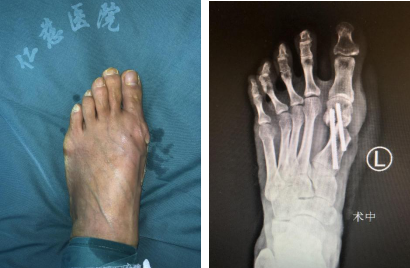

术后即刻

术后2个月

石荣剑副院长、曹广超主任、赵亮医生团队为患者行左足拇外翻矫形手术。术中于左足第一跖骨头端内侧做一长约5毫米微小切口,利用超声骨刀行跖骨远端外移截骨,远端向外侧推移、向跖侧下压,使用全螺纹空心螺钉固定。术后患者恢复良好。